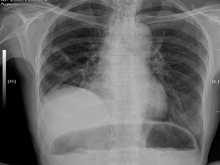

膈肌膨出

(又名膈肌膨隆)

膈肌膨出是指由于发育不全或炎症、损伤(包括出生时的膈神经损伤)等因素,膈肌萎缩为...

检查项目:

胸部B超、胸部MRI、胸部CT